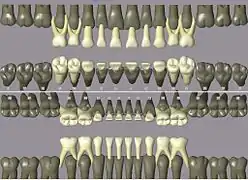

Codes, names, and usual number of roots: (see chart of teeth at Universal Numbering System)

- 11 21 51 61 maxillary central incisor 1

- 41 31 81 71 mandibular central incisor 1

- 12 22 52 62 maxillary lateral incisor 1

- 42 32 82 72 mandibular lateral incisor 1

- 13 23 53 63 maxillary canine 1

- 43 33 83 73 mandibular canine 1

- 14 24 maxillary first premolar 2

- 44 34 mandibular first premolar 1

- 15 25 maxillary second premolar 1

- 45 35 mandibular second premolar 1

- 16 26 54 64 maxillary first molar 3

- 46 36 84 74 mandibular first molar 2

- 17 27 55 65 maxillary second molar 3

- 47 37 85 75 mandibular second molar 2

- 18 28 maxillary third molar 3

- 48 38 mandibular third molar 2

ISO notation primary teeth